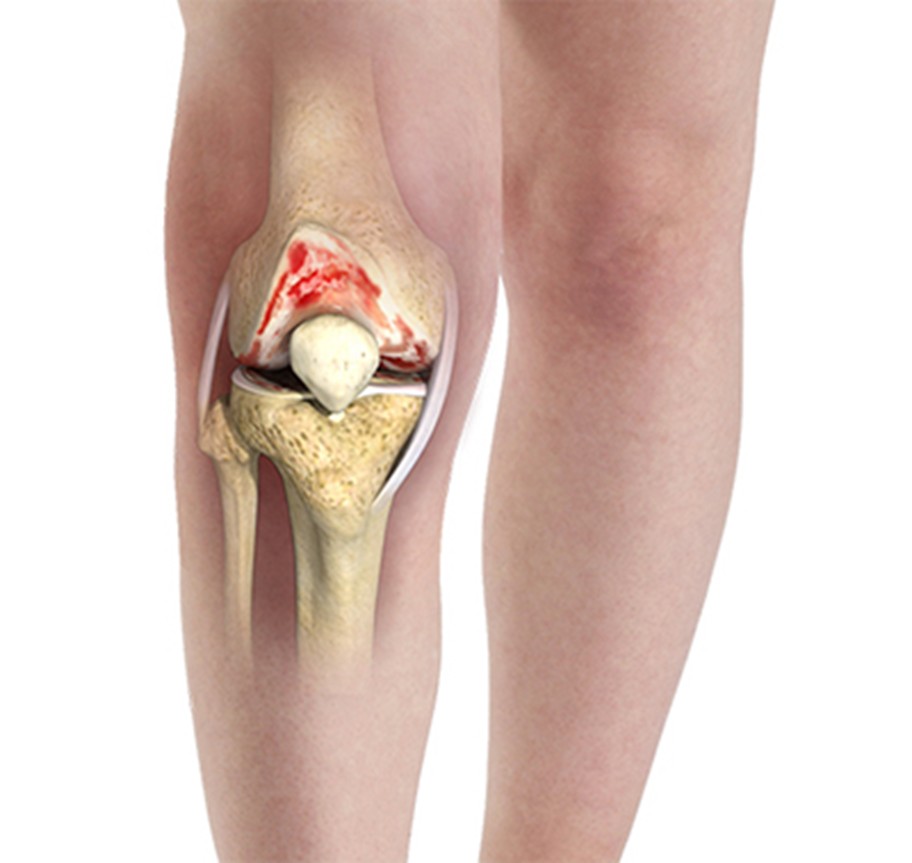

3 стадия (выраженная)

• значительное разрушение хряща

• деформация сустава

• постоянная боль (в том числе в покое)

• выраженное ограничение подвижности

• возможна хромота

4 стадия (тяжёлая)

• практически полное разрушение хряща

• резкая деформация сустава

• интенсивная постоянная боль

• почти полная утрата подвижности

• значительное нарушение функции конечности (вплоть до инвалидизации)

Когда показано оперативное лечение

Хирургическое вмешательство рассматривается в следующих случаях:

• выраженное разрушение суставного хряща

• сильная боль, не поддающаяся консервативному лечению

• значительное ограничение подвижности

• выраженная деформация сустава

• существенное снижение качества жизни

• отсутствие эффекта от длительной консервативной терапии

Оперативное лечение, как правило, требуется на 3–4 стадии гонартроза, когда происходит выраженная деформация сустава и стойкое нарушение его функции.